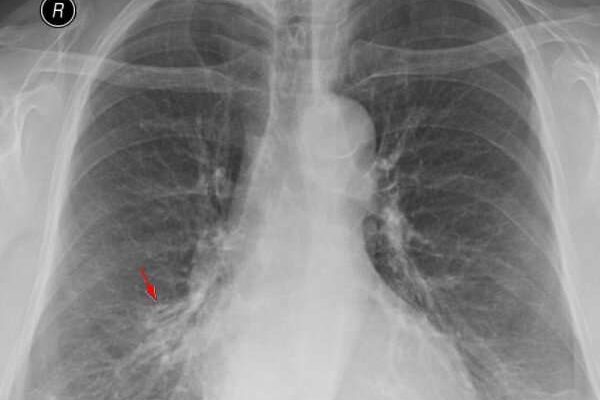

Самый распространенный метод диагностики легких — рентген грудной клетки. Однако, если врач подозревает, что у пациента есть спайки, пациента направляют на рентгенологическое обследование. На рентгеновском снимке синехии можно определить по мутным темным пятнам. Это похоже на затемнение тени и неподвижно на вдохе и выдохе.

Иногда обнаруживается деформация грудной клетки и диафрагмы. Чаще всего спайки обнаруживаются в нижней части легкого. Этот тип спаек называется плевродиафрагмальным, а тип спаек в верхней части — плевроапикальными.